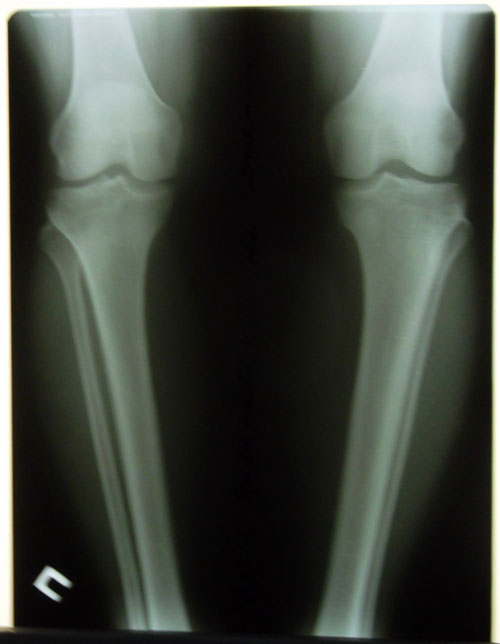

Дата операции 09.09.2015г.

Исходник.

53 года.